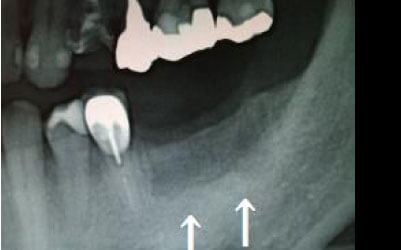

骨が薄い場合、そのままインプラントを行うのはお勧めできません。

ただし、事前に骨を増やす治療を行ったり、インプラントと同時に骨を増やす治療をすることで、インプラントは可能です。

1)インプラント治療を行う前に、骨の治療が必要かもしれません。

2)骨の治療から始めると、その分、治療期間が長くなります。

3)骨の治療は、通常のインプラント治療よりも難易度が高いため、経験の豊富な先生やインプラント認定医のいる歯科医院で治療を受けることをお勧めします。

4)骨の状況をしっかり把握するためにも、CT撮影が必須となります。